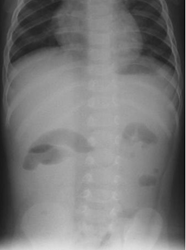

In paralytic ileus, there is too much gas in both small and large bowels (Figure 4 & 5).

Figure 5 Anteroposterior supine abdominal radiograph in a 9-month-old infant with abdominal distention following diarrhea showing dilatated bowel loops with smooth walls scattered throughout the abdomen haphazardly with presence of gas in the rectum suggestive of paralytic ileus.

In paralytic ileus there is uniform dilatation of bowel to the level of the rectum (Figure 4 & 5).

In paralytic ileus, there are few and less dilated air fluid levels scattered throughout the abdomen (Figures 4 & 5).

In paralytic ileus, the loops are scattered disorderly throughout the abdomen (Figures 4 & 5).